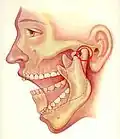

Die Gow-Gates-Technik (benannt nach dem Erstbeschreiber, dem Australier George Gow-Gates) wurde 1973 entwickelt, um die Misserfolgsquote der Leitungsanästhesien auf nur 5 % zu vermindern. Mittels einer einzigen Injektion werden mehrere Leitungsanästhesien, nämlich des Nervus alveolaris inferior, des Nervus lingualis, des Nervus mylohyoideus, des Nervus auriculotemporalis und – mit 75-prozentiger Wirkung – auch des Nervus buccalis, durchgeführt. Hierzu wird ein Depot des Lokalanästhetikums am Kondylenhals des Unterkiefers gesetzt.[51] Bei weit geöffnetem Mund wird an der Incisura intertragica der Kondylenkopf ertastet und dient als „Zielmarke“. Die Injektionsnadel (Gaugegröße 27) wird zu zwei Dritteln in die Umschlagfalte hinter dem Tuber maxillae in den paratubären Raum eingeführt und der Knochenkontakt am Kondylenhals gesucht. Der Nervenstrang selbst liegt distal des Kondylus. Nach Aspirationstest und erfolgter Injektion soll der Patient den Mund eine weitere Minute weit geöffnet halten. Wegen der geringen vaskulären Versorgung dieses Bereichs und des dadurch verlangsamten Abtransports des Lokalanästhetikums wird ein Lokalanästhetikum (Mepivacain – Scandicain, Meaverin) ohne Vasokonstriktor verwendet. Die Injektion ist für den Patienten kaum wahrnehmbar.[52] Der Patient sollte zuvor aufgeklärt werden, dass bei der Gow-Gates-Lokalanästhesie eine Gesichtshälfte mehr oder minder vollständig anästhesiert sein wird.

Vorschubbewegung des Unterkiefers bei der Mundöffnung

Vorschubbewegung des Unterkiefers bei der Mundöffnung -